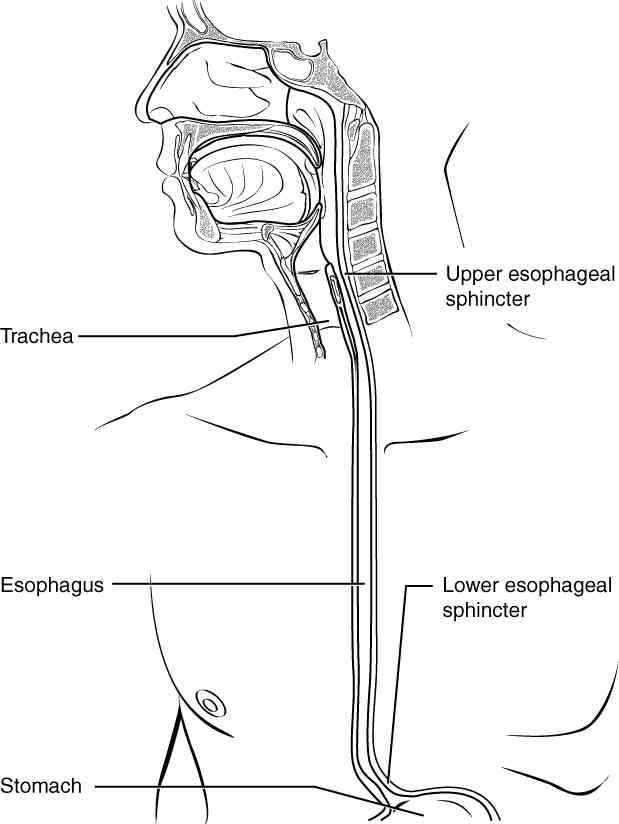

This page is under construction. For now, it is just a resource of the images found in the OpenStax Anatomy and Physiology Handbook. It wil slowly change into a revision tool. Each slide has a number. Use this to refer to the slide. When completed, it will have an unlabelled section, with labelled slides in parallel. On the unlabelled slides, write your answer and use the labelled slide to assess yourself. Keep track by also noting the number on each slide. Improvement at each attempt is important, more so than full marks on a first attempt.